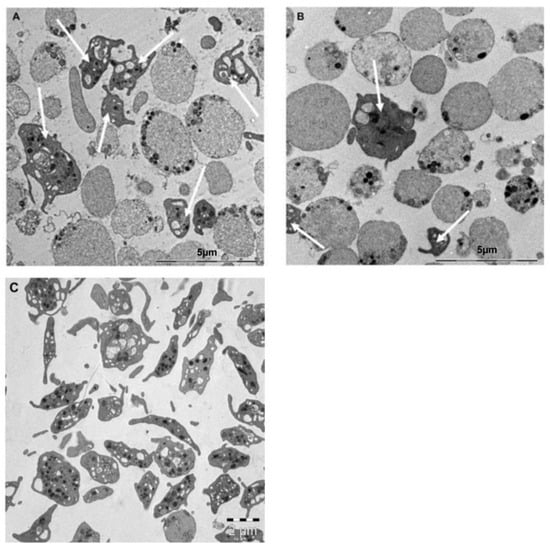

2.7. DMSO and DMSO-Free Platelets Display Similar Ultrastructural Changes through TEM Imaging